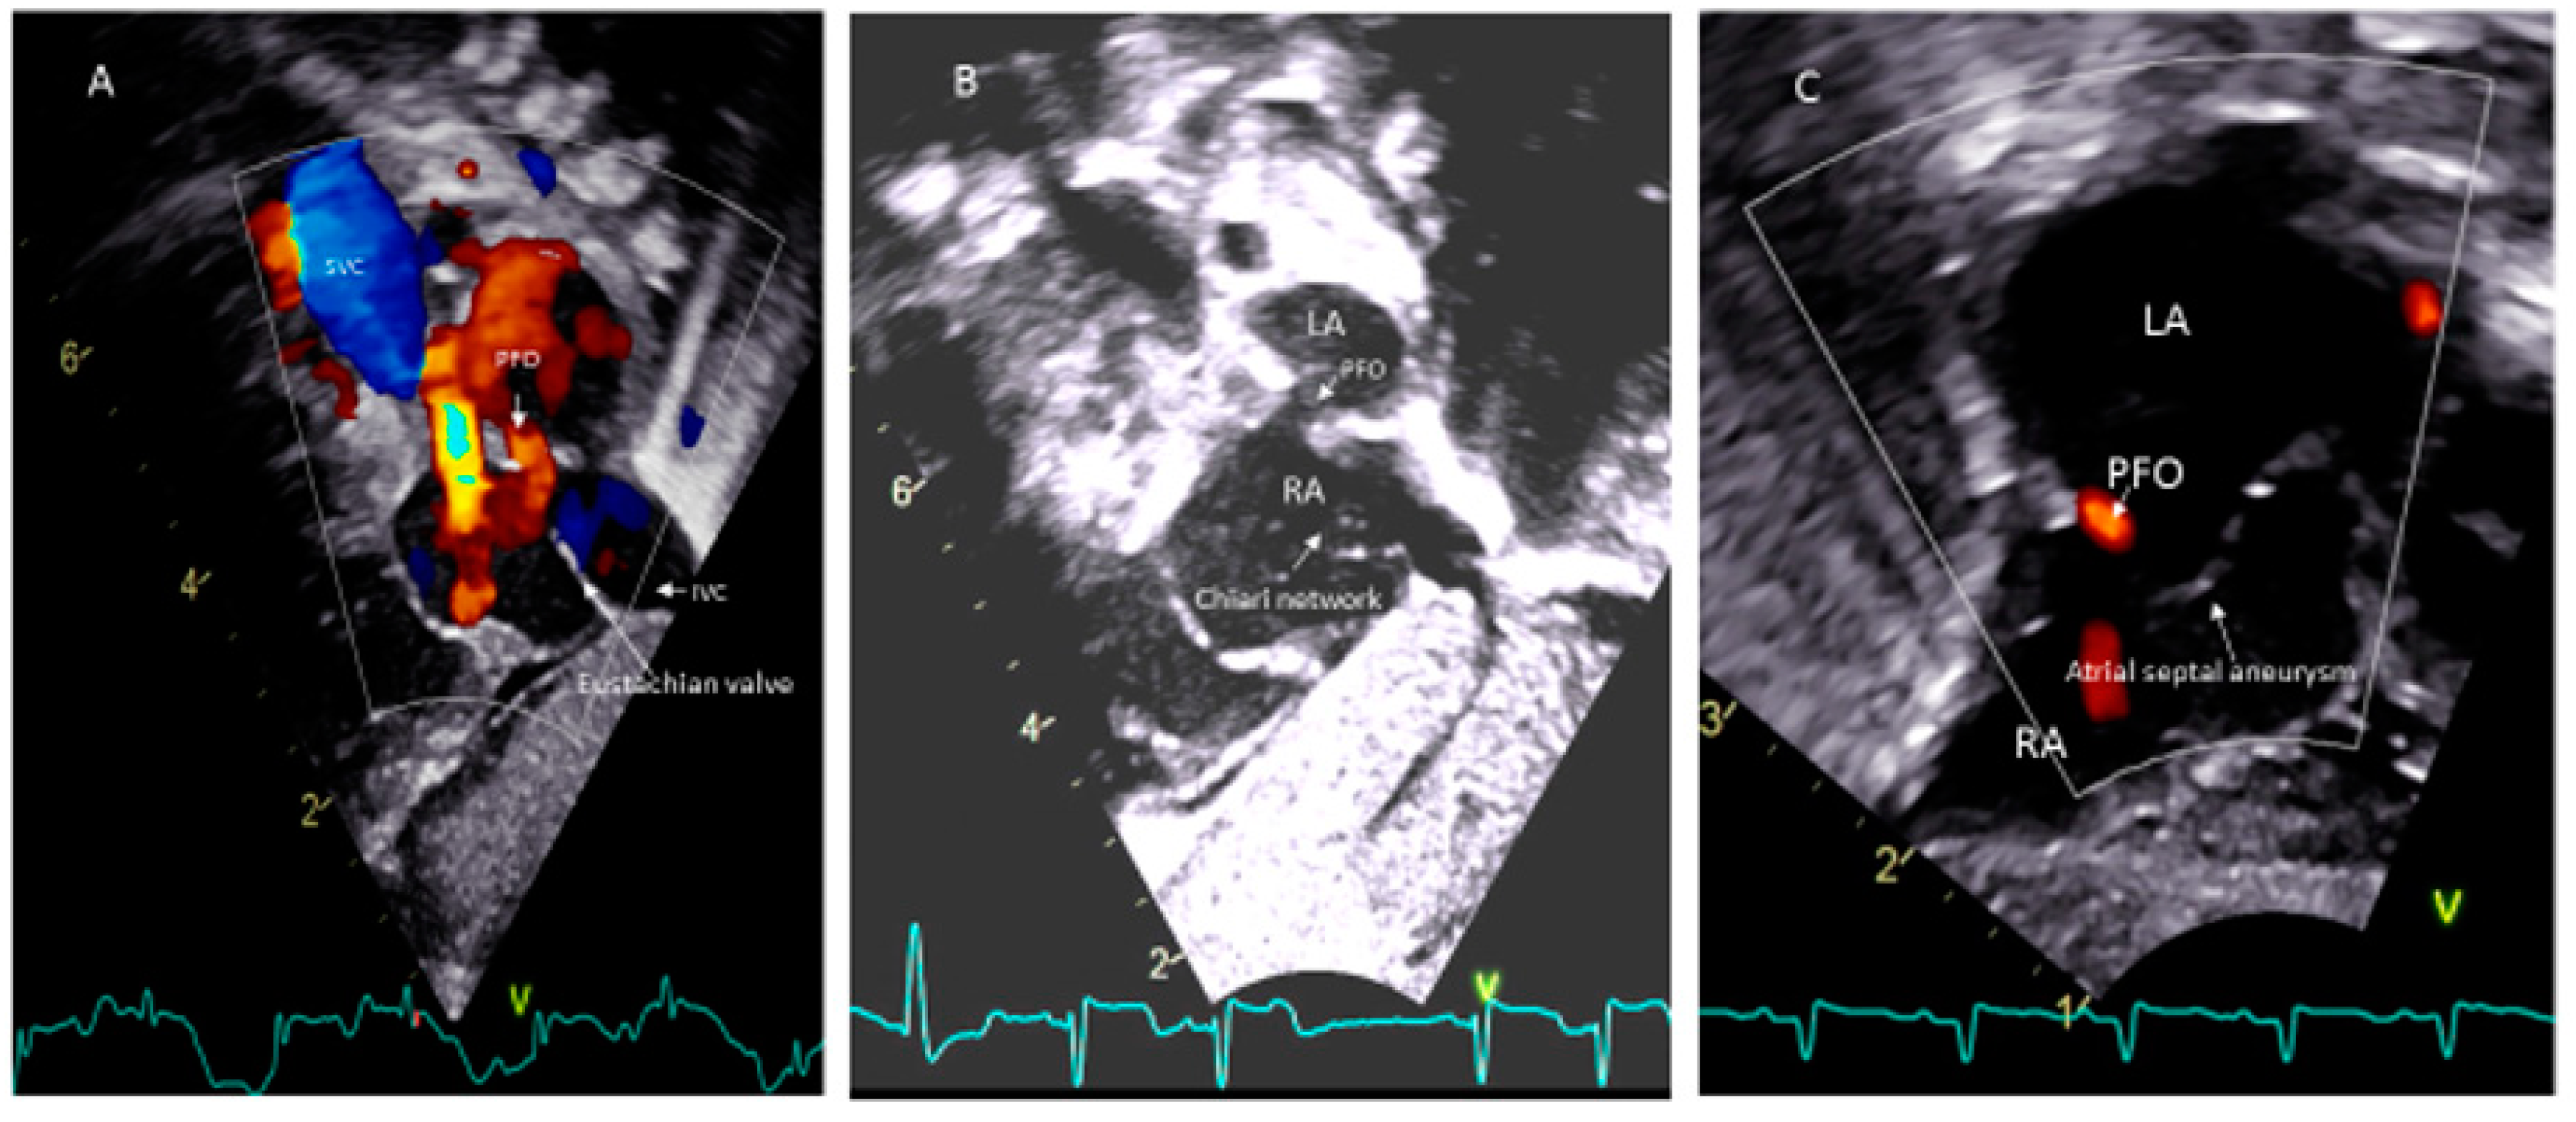

- Schneider, B.; Hofmann, T.; Justen MHMeinertz, T. Chiari’s network: Normal anatomic variant or risk factor for arterial embolic events. J. Am. Coll. Cardiol. 1995, 26, 203. [Google Scholar] [CrossRef]

- Rigtelli, G.; Dell’avvocata, F.; Braggion, G.; Giordan, M.; Chinaglia, M.; Cardaioli, P. Persistent venous valves correlate with increased shunt and multiple preceding cryptogenic embolic events in patients with patent foramen ovale: An intracardiac echocardiographic study. Catheter. Cardiovasc. Interv. 2008, 72, 97. [Google Scholar] [CrossRef]

- Hanley, P.C.; Tajik, A.J.; Hynes, J.K.; Edwards, W.D.; Reeder, G.S.; Hagler, D.J.; Seward, J.B. Diagnosis and classification of atrial septal aneurysm by two-dimensional echocardiography: Report of 80 consecutive cases. J. Am. Coll. Cardiol. 1985, 6, 1370–1382. [Google Scholar] [CrossRef]

- Mas, J.L.; Arquizan, C.; Lamy, C.; Zuber, M.; Cabanes, L.; Derumeaux, G.; Coste, J. Recurrent cerebrovascular events associated with patent foramen ovale, atrial septal aneurysm, or both. N. Engl. J. Med. 2001, 345, 1740–1746. [Google Scholar] [CrossRef]